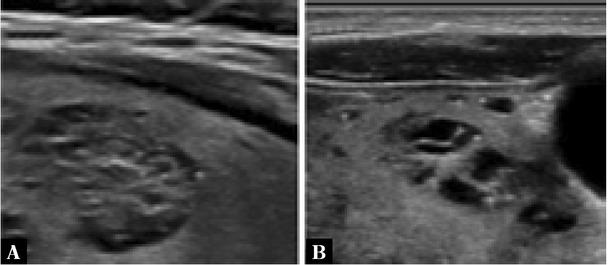

Fig. 4

Greyscale sonographic images of thyroid nodules with heterogeneous echogenicity: A. a mixed isoechoic and hypoechoic thyroid nodule (since >50% of the nodule is hypoechoic, this will be the descriptor selected for scoring); and B. a 50% isoechoic and 50% hypoechoic thyroid nodule (in this case, the more conservative ‘isoechoic’ descriptor will be selected for scoring)